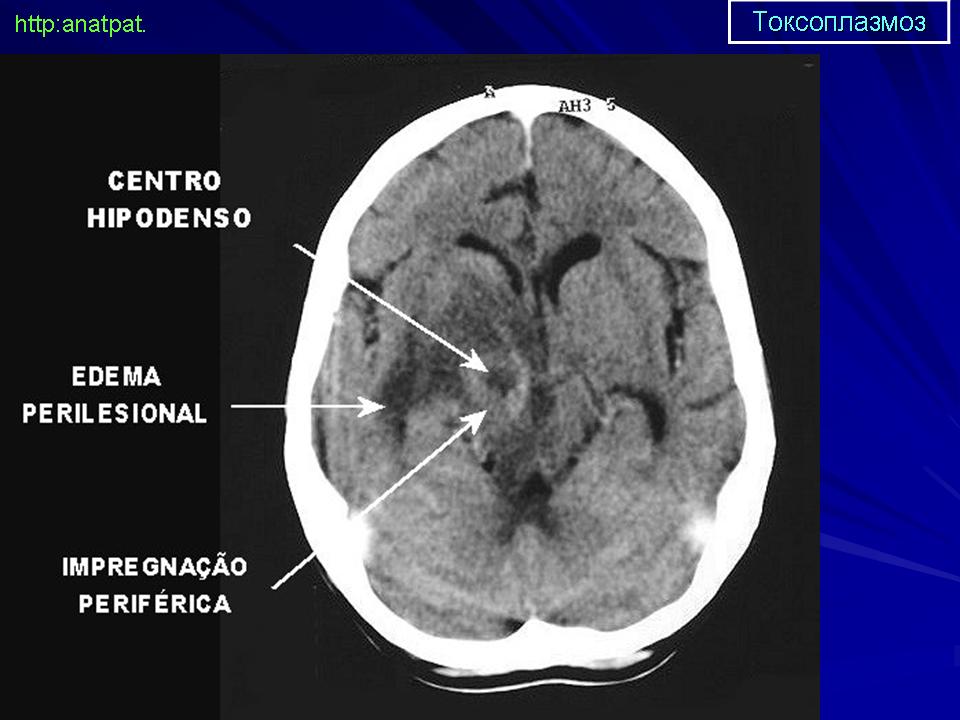

Церебральный токсоплазмоз.

Церебральный токсоплазмоз

Neurotoxoplasmosis

Дифференциальная диагностика изображения